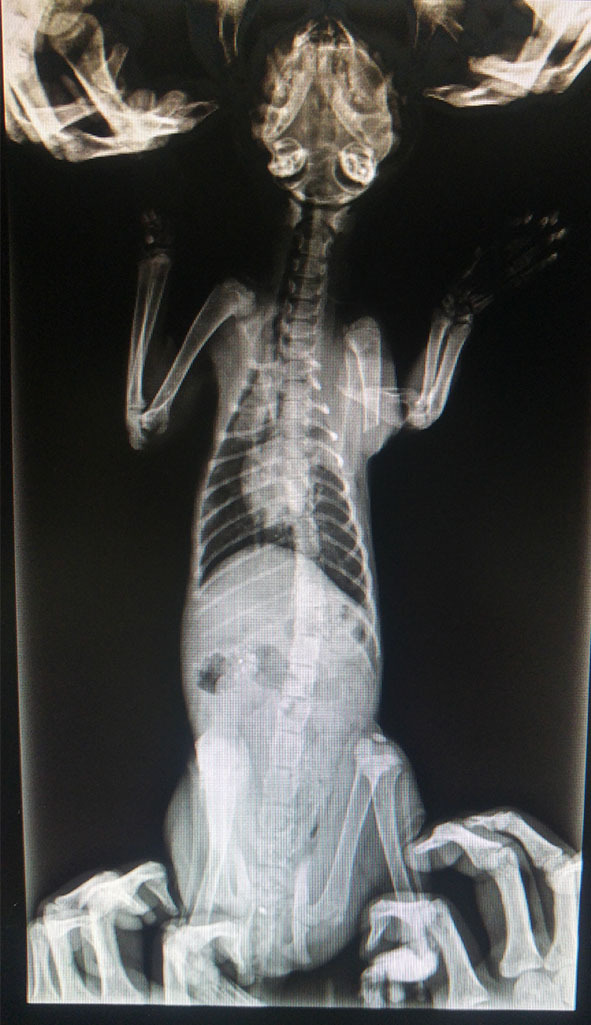

主題: 車禍的小橘貓 申請者姓名: 陳宇蓁 花色: 申請日期: 2016-10-10 22:43:31 申請者部落格: 申請者臉書網址: https://www.facebook.com/atotal.chen 所在縣市/合作醫院: 台中市/春天動物醫院 治療費用: 7000元 需求人數: 15人 已結案 (2016-12-22 01:49:07) 報名人員: 湯圓&小甜甜(已付款)、小雷、小雷(已付款)、習木.惜木(已付款)、Kuen-Lin Tsai(已付款)、tigercat(已付款)、jojolin(已付款)、wgs(已付款)、Angus Chuang(已付款)、瑪咪(已付款)、三毛(已付款)、sandy(已付款)、陳昱先 x3(已付款)、以四面佛名義捐款(已付款)、 候補人員: 動物病情說明: 8/19 在五權西路近文心路口的全聯前面撿到車禍的小橘貓,馬上送到全國動物醫院,醫生照X光表示左前腳斷了,口腔有血,X光看起來胸腔疑似出血,需24小時吸氧觀察,因為全國住院比較貴,所以又轉送文心路中港路口慈愛看住院,慈愛醫生幫她上營養跟消炎止血點滴。小橘一臉看起來很恐慌,只要有人靠近便低聲嘶吼!

8/20 下午3點去慈愛把小橘轉院到協會指定春天醫院,醫生診斷小貓算穩定也可以進食,噴除蚤劑+開了3天的消炎藥,便讓我帶回家看護,星期一再帶去回診。小橘其實看起來很虛弱,醫生叫我帶回家看護我緊張得要死,好怕牠翹了...

8/22 每天三小時一次的餵食持續2天小橘不會吼人了,早上送到春天動物醫院,重新照了一次X光片,將斷掉的左手上石膏,做血檢、傳染病檢查,醫生送了消炎藥跟驅蟲藥。傍晚接牠回來的時候心情很不爽,可能是左腳的疼痛,讓他"罵罵號"一整晚...

8/31 複診照了X光片,醫生說復原照進度算還不錯,但以後難免有點小小頗腳,聽完心有點酸酸的,擔心牠以後找不到好人家愛牠一輩子...

9/13 複診照X光拿6天的藥,醫生說骨頭恢復情況良好也長胖了!一切算順利康復著!

9/29 複診再照一次X光看骨頭情況,醫生說還不錯,一個月這樣順恢復很厲害了,這是最後一次看診。我是第一次撿到流浪貓,非常的手足無措,很謝謝這期間幫忙過我的人!另外更謝謝在這社會角落照顧流浪動物的愛媽們的辛勞,妳們真的好偉大~動物近況說明: 小貓現在食慾良好,也調皮愛玩,不過牠走路有時還會縮著左腳,按摩持續在做,希望能盡量讓牠恢復正常人生。